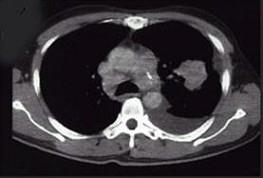

问题 女,68岁,咳嗽伴胸痛胸闷一月,CT检查如图,最可能的诊断为 ( )

选项 A、左上肺软骨肉瘤伴胸膜转移 B、左上肺结核 C、左上肺周围型肺癌伴胸膜转移 D、左上肺血管瘤 E、左上肺不张

答案 C